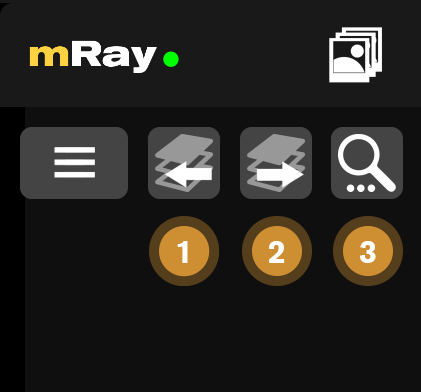

10.1. Serien-Buttons

Die Serien-Buttons erscheinen nur, wenn es zur aktuell betrachteten Studie weitere Serien gibt.

-

Geht zur vorherigen Serie in der Studie

-

Geht zur nächsten Serie in der Studie

-

Suche nach zugehörigen Studien